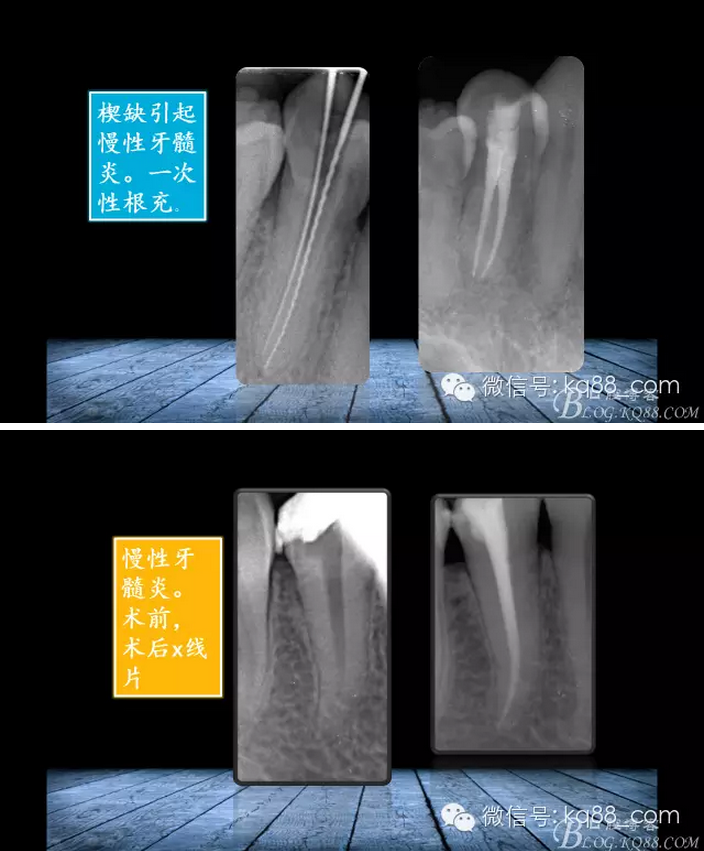

張瑞鋒:簡(jiǎn)單的事情認(rèn)真做——我的根管治療